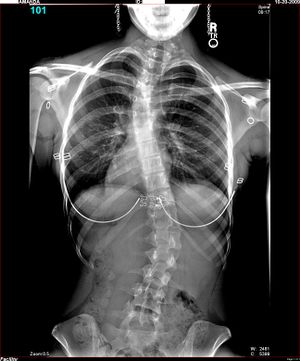

جنف فتاة قوقازية عمرها 16 سنة؛ آشعة سينية أمامية، واقفة، بملابسها | |

الجنف Scoliosis قوس جانبي يصيب العمود الفقري. وفي معظم الحالات يصبح هذا الوضع ظاهرًا في فترة المراهقة أو قبل ذلك. ويصيب الجنف البنات أكثر من البنين، لكن الأطباء لا يعرفون سببًا لذلك. وقد تؤدي الحالات المتقدمة أيضًا إلى تشوه شديد قد يؤثر في القلب والرئتين والجهاز العصبي. وهذا التشوه يمكن أن يؤدي أيضًا إلى مشاكل نفسية. والأطباء لا يعرفون سبب الإصابة في معظم الحالات، لذلك فإن بعض الحالات تنتج من أمراض في العضلات أو نتيجة تشوهات خلقية عند الميلاد.